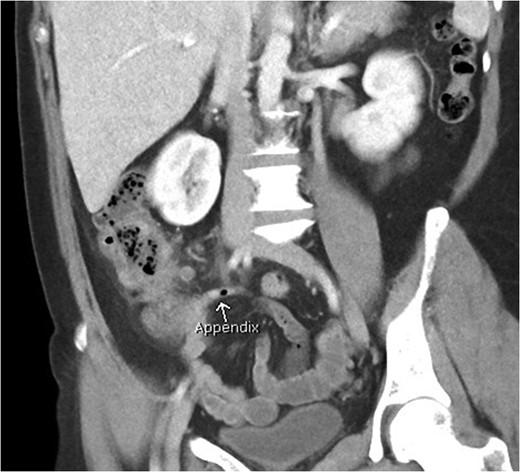

Coronal view of patient with caecal carcinoma. Normal (non-dilated) appendix (arrow).